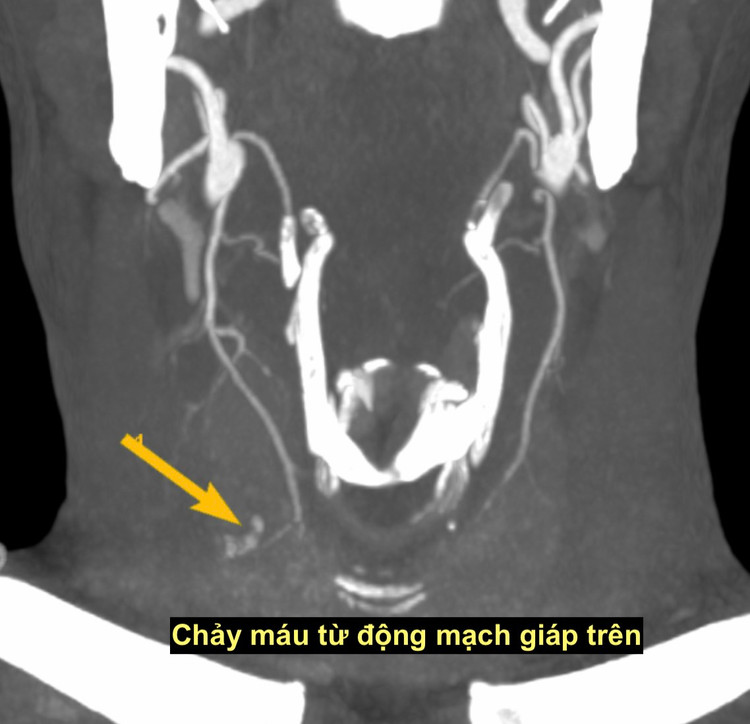

Bệnh viện Đại học Y vừa tiếp nhận một bệnh nhân chảy máu nghiêm trọng sau chọc tế bào tuyến giáp. Một bệnh nhân sau khi chọc tế bào tuyến giáp buổi sáng, đến trưa xuất hiện căng tức vùng cổ, mệt mỏi, nhợt nhạt. Khi vào khoa Cấp cứu, chụp chiếu phát hiện khối máu tụ lớn vùng cổ kèm ổ chảy máu hoạt động ở thùy phải tuyến giáp.

Bệnh nhân nhanh chóng được chuyển ngay sang phòng can thiệp nút mạch cầm máu. Kết quả chụp mạch cho thấy một nhánh động mạch tuyến giáp bên phải đang chảy máu. Bệnh nhân ngay lập tức được can thiệp nút mạch cầm máu, may mắn qua khỏi tình trạng nguy hiểm.